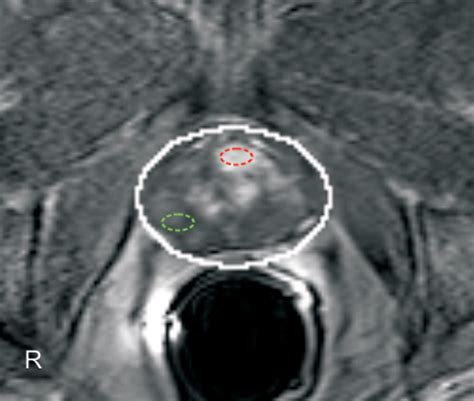

• Multiparametric MRI (mpMRI): This technique combines multiple MRI sequences, including T2-weighted imaging, diffusion-weighted imaging (DWI), and dynamic contrast-enhanced (DCE) imaging, to provide a comprehensive evaluation of the prostate.

• Prostate Imaging Reporting and Data System (PI-RADS): This standardized reporting system helps radiologists interpret MRI findings and classify the likelihood of clinically significant prostate cancer.